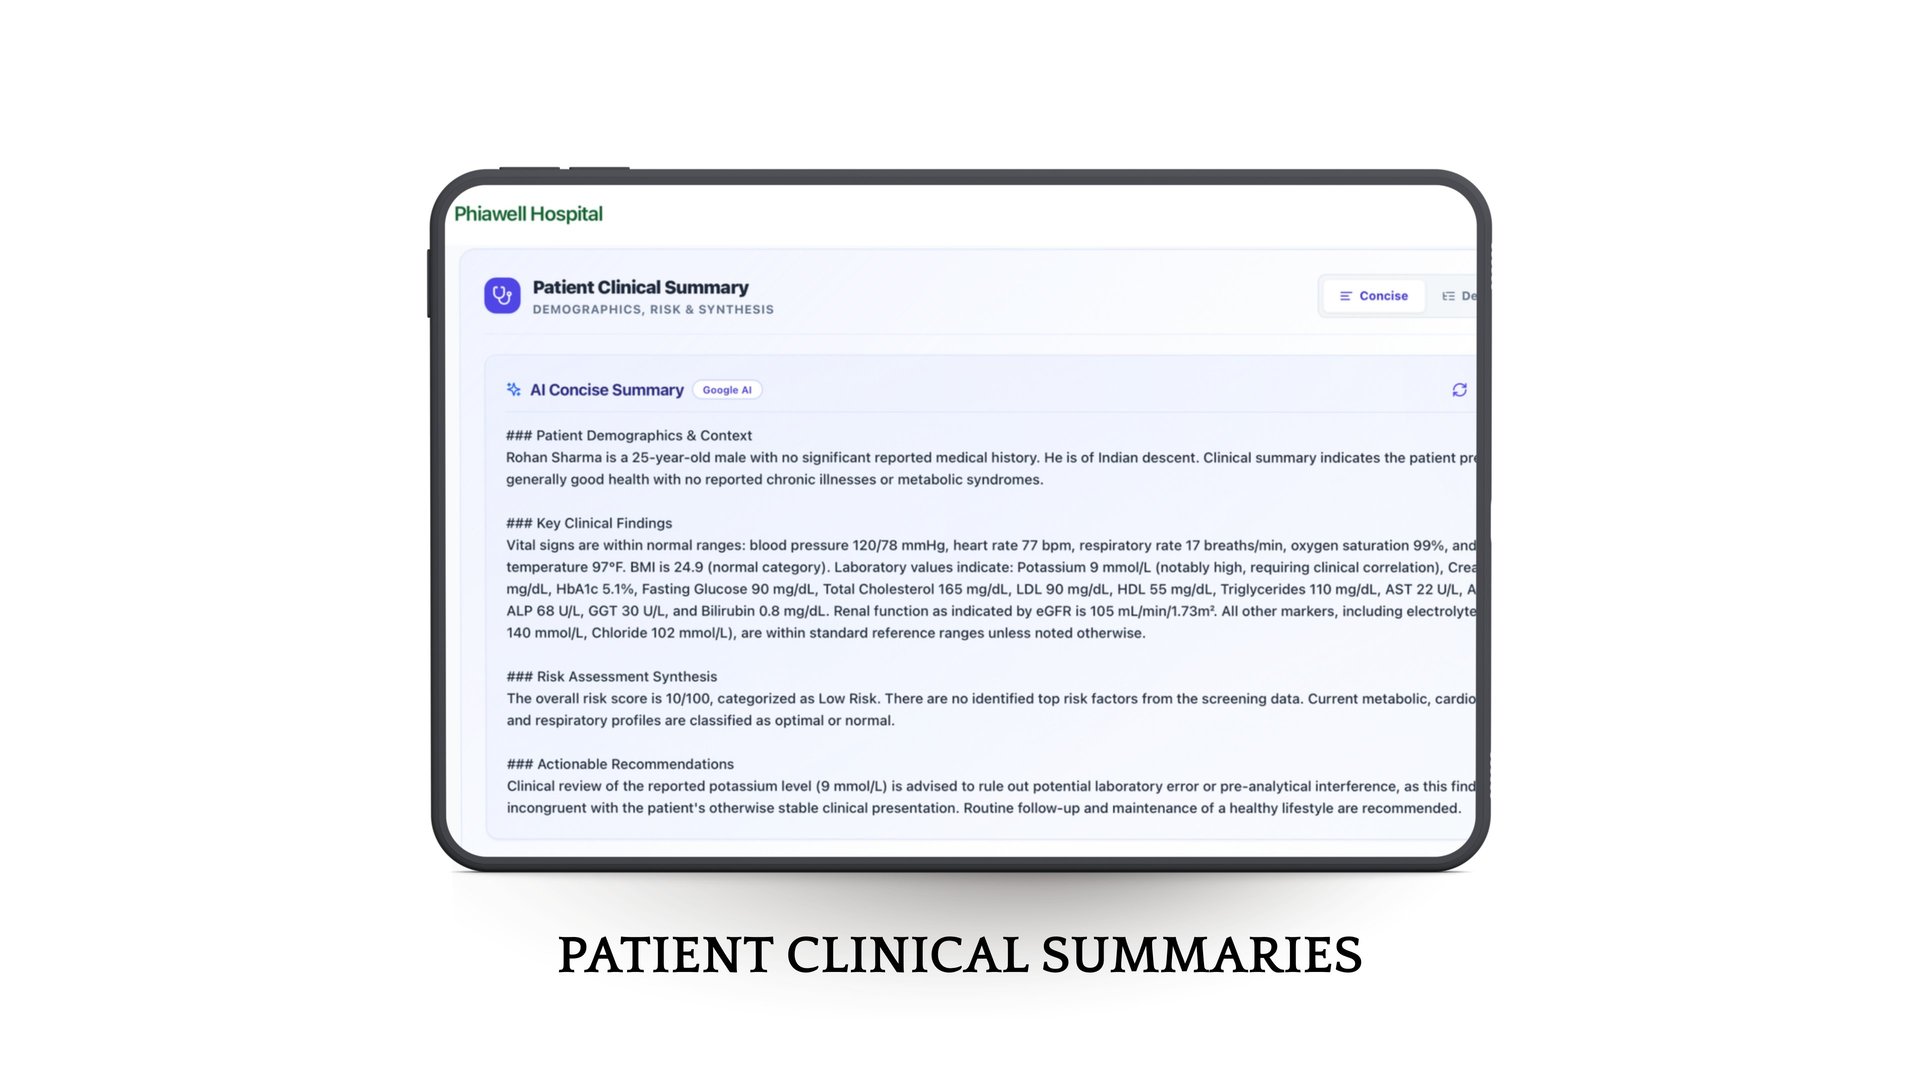

Intelligent Health Insights

With built-in risk assessment, smart analytics, and concise patient summaries, doctors can make faster, more accurate decisions while shifting towards preventive care.

Phia.Care's Risk Assessment Models

Phia.Care's Risk Assessment Models use clinically recognized algorithms, including WHO-based risk evaluation frameworks, to analyze patient screening data and generate structured health risk insights.

By evaluating vitals, demographics, and other screening parameters, the system creates a standardized risk profile for each patient and assigns a confidence score based on data completeness. This helps clinicians quickly understand potential health risks and support early, informed medical decisions.